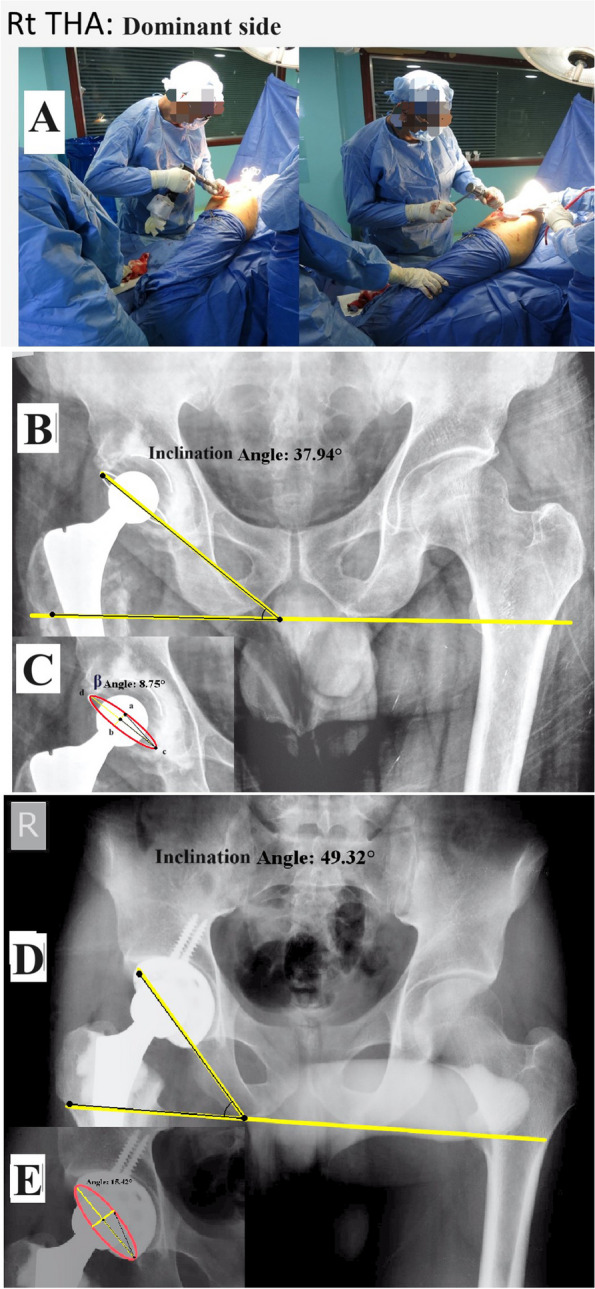

Methods: Cup inclination and anteversion of 420 THAs were radiographically evaluated retrospectively. THAs were performed by a senior right-handed surgeon, who operated through a direct lateral approach in a lateral decubitus position using manual instruments and freehand technique for cup placement. Patients were assigned to two groups: Group A (right, or dominant side), and Group B (left, or non-dominant side), with equal cases of THAs (n = 210) in each group.

Results: No difference was found in patients' basic characteristics, preoperative diagnosis, and cup fixation (54.3% cemented and 45.7% cementless) between the two groups. There was a significant difference in cup inclination between Groups A and Group B (40.1° ± 6.3° vs. 38.2° ± 6.1°) (P = 0.002). No significant difference was revealed in anteversion between the two groups (11.7° ± 4.4° vs. 11.8° ± 4.7°) (P = 0.95). The percentage of cups located within the safe zone in terms of both inclination and anteversion was 85.2% vs. 83.8% and 69% vs. 73.3% for Group A and Group B, according to Lewinnek and Callahan's safe zones, respectively. There existed a significant difference in the cemented cup inclination between Group A and Group B (40.8° ± 6.4° vs. 38.3° ± 6.3°) (P = 0.004).

Conclusion: Cup inclination is affected by the surgeon's handedness when operating through a direct lateral approach and using a freehand technique, while anteversion is less affected. Furthermore, the difference is greater with cemented cups.